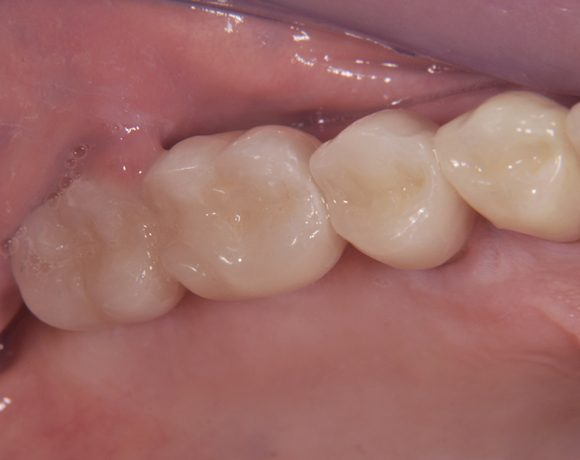

Der vorliegende Patientenfall zeigt eine komplette Neuversorgung der vorhandenen Metallkeramikkronen mit vollkeramischen Restaurationen. Zusätzlich wurde im Oberkiefer die Zahnreihe mit zwei Implantaten, für die fehlenden Molaren, ergänzt. Da keine ausreichende Knochenhöhe vorhanden war wurde ein interner Sinuslift geplant.